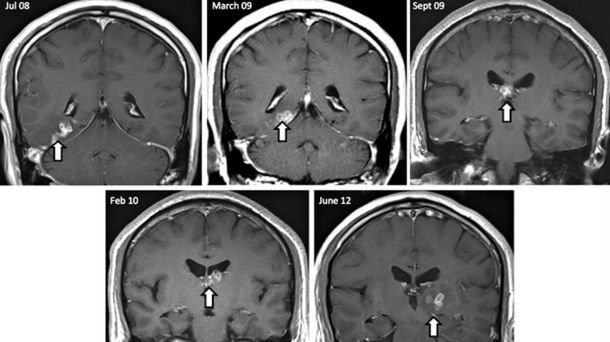

Después de visitar a su médico, una resonancia magnética reveló un grupo de anillos en el lóbulo temporal derecho.

Después de someterse a dos biopsias, los cirujanos encontraron el gusano moviéndose en su cerebro y lo quitaron en 2012. Luego, el hombre se dio medicamentos para ayudar a tratar la infección, pero él sigue sufriendo de problemas asociados con haber tenido el gusano que vive en su cerebro.